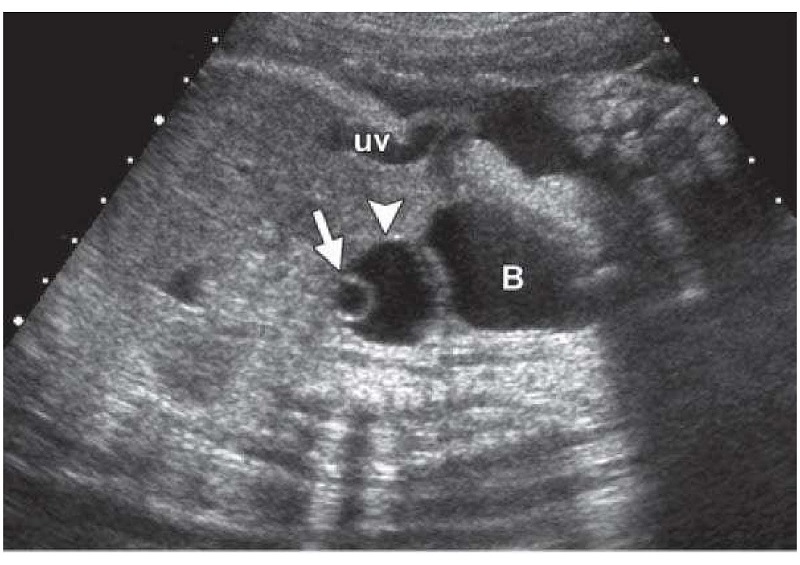

Hội chứng buồng trứng đa nang (PCOS) là một rối loạn nội tiết phổ biến, đặc trưng bởi sự hiện diện của nhiều nang trứng nhỏ (thường >12 nang, kích thước 2-9mm) và rối loạn rụng trứng mạn tính (Theo Tiêu chuẩn Rotterdam, 2003).

Ảnh trên: Hội chứng buồng trứng đa nang (PCOS)

Tại sao PCOS gây ra nhiều nang nhỏ?

Trong PCOS, sự mất cân bằng hormone (thường là nồng độ LH/FSH cao và kháng insulin) cản trở quá trình chọn lọc nang vượt trội, khiến nhiều nang bị “mắc kẹt” ở giai đoạn phát triển sớm (Theo Hiệp hội Nội tiết Hoa Kỳ). Các nang này không thể trưởng thành để rụng trứng.

Phương pháp phổ biến và chính xác nhất để theo dõi sự phát triển (kích thước và số lượng) của nang trứng là siêu âm qua ngã âm đạo (transvaginal ultrasound) (Theo Tạp chí Siêu âm trong Y học).

Siêu âm nang trứng vào ngày nào của chu kỳ?

Để đánh giá dự trữ buồng trứng, bác sĩ thường chỉ định siêu âm vào ngày 2 hoặc 3 của chu kỳ để đếm số nang cơ sở (AFC) (Theo ASRM). Để theo dõi sự phát triển cho hỗ trợ sinh sản, siêu âm được lặp lại nhiều lần từ khoảng ngày 10 cho đến khi xác nhận rụng trứng.